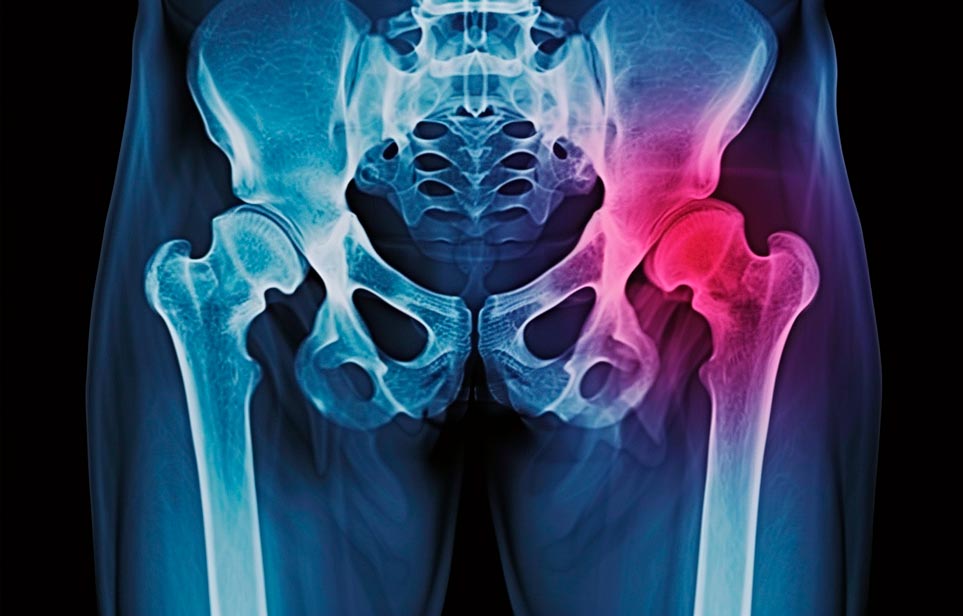

Реабилитация пожилых после перелома шейки бедра в Красноярске

Эффективная и профессиональная реабилитация после перелома шейки бедра в Красноярске осуществляется по демократичным ценам лучшими специалистами современной медицинской клиники «Заботливые люди» с применением персонального подхода к каждому пожилому человеку с такой тяжёлой травмой бедренной кости ноги. В процессе осуществления такой специализированной услуги все наши пациенты имеют возможность получения качественного и достойного обслуживания, эффективного восстановления. Лучший дом престарелых позаботиться о Вашем близком человеке.

Такая травма в большей части случаев возникает у граждан преклонного возраста. При её появлении на протяжении длительного времени сохраняются болевые и неприятные ощущения в области паха, при которых серьёзно ухудшается качество жизни, возникает множество последствий для его жизни и здоровья.

По какой симптоматике можно определить перелом шейки бедра

- Визуально повреждённая нога сокращается на несколько сантиметром из-за сокращения мышц.

- Стопа выворачивается наружу.

- В лежачем положении человек не может поднять ногу.

При такой симптоматике важно незамедлительно обращаться к специалистам для получения всей необходимой помощи, терапии и восстановления после перелома шейки бедра. Если не оказать помощи старику, то это приведёт к гноению, инвалидности, иным видам осложнений.